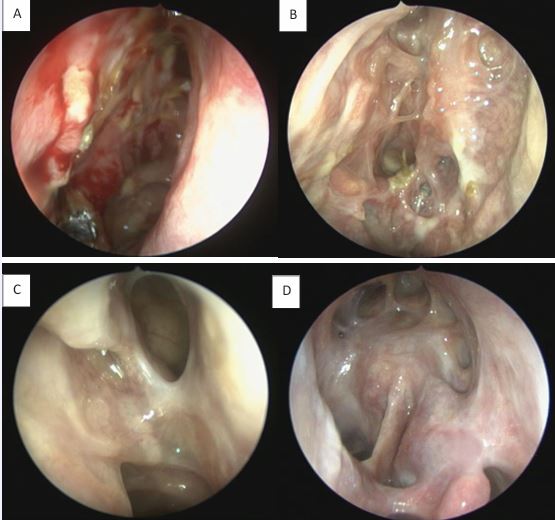

The olfactory mucosa of severe uncontrolled CRSwNP also presents typical markers of Type-2 inflammation (IgE, IL4, IL5, ECP, CCL3 and CCL4), similar to the pattern present in the nasal polyps. Patients post-Reboot demonstrated significant improvement in olfactory function, with significant response at just 1 month post-operatively and continued improvement at 2 years of follow-up. In contrast, ESS surgery showed improvement in olfactory function in the short-term follow-up, but worsened smell in the long term; Reboot also showed lower recurrence rates of nasal polyps when compared to ESS surgery at 2-year follow-up [17-24].Type-2 inflammation in nasal polyps is associated with worse impaired sense of smell before surgery but with a significant better olfactory improvement after Reboot. In other words, the more severe the Type-2 inflammation is in the polyps pre-operatively, the more significant the olfactory improvement is in the Reboot post-operative. There is no significant correlation between smell and Type-2 inflammation in the olfactory mucosa tissue, before or after surgery. Possibly, Type-3 inflammation in the olfactory mucosa is associated with better pre operative smell, but worse olfactory evolution after Reboot [24]. Postoperative nasoendoscopy images show that, by keeping the periosteum as intact as possible during surgery, the sinus mucosa re-epithelializes on average within 2 weeks, following with satisfactory long-term evolution (Figures 6 and 7).

Figure 7 Postoperative follow-up after Reboot surgery. A) Right nasal cavity, 14 days; B) Right nasal cavity, 30 days; C) Left nasal cavity, 90 days; D) Left nasal cavity, DRAF III, 24 months.